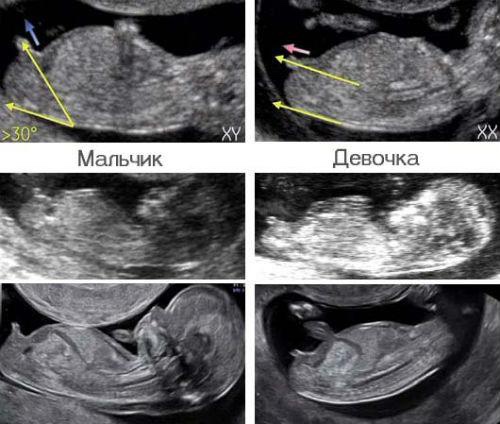

У кого совпало?😂

Это в каком сроке?

примерно 11-14 недель

@_l_e_r_i_ так в 12 недель мне ушла пол говорили. По этому ли признаку или нет, но 2 все сошлось. Разве нет?

@elive, не поняла вопрос)))Просто хочу проверить достоверность картинок)